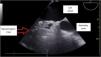

A 66-year-old patient on the second day after biological mitral valve replacement surgery due to severe periprosthetic insufficiency. While extubated, he developed tachycardia, hypoperfusion and hyperlactacidemia, with the need for vasopressor medication and the deobstruction of drains due to large clots, followed by clinical improvement. This was followed by repeat worsening with the same clinical manifestations, requiring intubation and vasopressor medication. Transesophageal ultrasound showed an anterior hyperdense mass with a minimal right atrial imprint (Fig. 1) and left massive pleural effusion at apical-middle and basal level, with “hematocrit sign” (Fig. 2). The thoracic CT scan showed an anterior mediastinal hematoma with posterior communication with the left pleura, and contrast leakage at the internal mammary artery level (Fig. 3), requiring urgent surgery and polytransfusion (see Supplementary material). In recent years, transesophageal pulmonary ultrasound has experienced marked development in critical patients, affording an excellent complementary tool for assessing the posterior and deep regions of the lung with increased imaging quality.